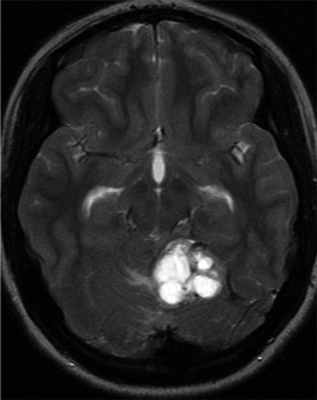

Гемангиобластомы ЦНС могут выявляться в детском возрасте, однако средний возраст диагностирования составляет 29 лет [32, 45, 46]. VHL-ассоциированные гемангиобластомы выявляются в среднем на 15 лет раньше, чем спорадические [47]. В зависимости от размера и местоположения опухоли клинические признаки гемангиобластомы ЦНС включают головную боль, тошноту, головокружение, атаксию, расстройство координации движений, нистагм, расстройства речи. Гемангиобластома спинного мозга может приводить к слабости конечностей и парестезиям. Диагноз устанавливается с помощью МРТ головного мозга и позвоночника. Гемангиобластомы обычно характеризуются медленным ростом и имеют высокий риск кровотечений, часто являются мультифокальными. Понимание патогенеза заболевания важно для выбора оптимального времени скрининга на опухоли и лечение [19]. Исследование тканей ЦНС умерших пациентов помогло пониманию гистогенеза гемангиобластом [49]. Активация фактора, индуцирующего гипоксию 2-альфа (HIF 2-α) происходит в маленьких мезенхимальных опухолях и в мезенхимальном компоненте больших опухолей. Активация HIF 1-α наблюдается в эпителиальном компоненте. Это позволило предполагать, что поражение ЦНС при VHL-синдроме — длительный процесс гемангиобластической пролиферации и дифференцировки [50] (рис. 2). Рисунок 2. Гемангиобластома ЦНС.